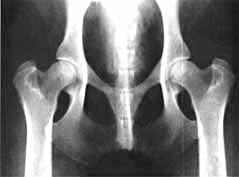

Gesunde Hüftgelenke (Baal "vom Gehrensee" - Aufnahme ohne Narkose)

Die Hüftgelenksdysplasie (HD) ist eine erblich bedingte Erkrankung. Als hauptsächliche Ursache und auslösender Faktor wird die Lockerheit des Hüftgelenks angesehen. Gelenkkopf und Gelenkpfanne nutzen sich dadurch verstärkt ab und verursachen bei Bewegungen Schmerzen.